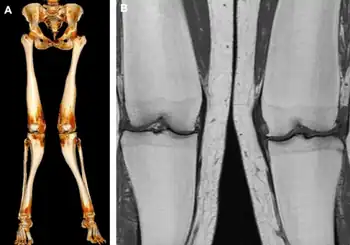

a,b)MRI and CT of Pyle disease (metaphyseal dysplasia)

Metaphyseal dysplasia, or Pyle disease,[3] is a disorder of the bones. It is a rare disease in which the outer part of the shafts of long bones is thinner than normal and there is an increased chance of fractures. Its hallmark feature is an abnormality of the long bones in the arms and legs in which the ends (metaphyses) of the bones are abnormally broad; the shape of the bones resembles a boat oar or paddle. The broad metaphyses are due to enlargement of the spongy inner layer of bone (trabecular bone). Although trabecular bone is expanded, the dense outermost layer of bone (cortical bone) is thinner than normal. As a result, the bones are fragile and fracture easily. The bone abnormalities in the legs commonly cause knock knees (genu valgum) in affected individuals.